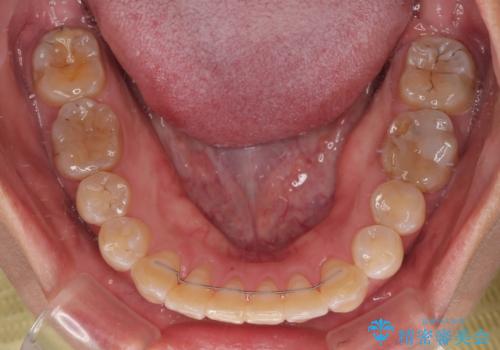

全く目立たないワイヤー矯正 上下裏側矯正

- リンガル

途中転勤や出産があり、通院できない期間が長くありましたが、無事に歯列を整えることができました。

- 矯正治療後の保定が不十分だと後戻り(元の位置に戻ろうとする動き)をします